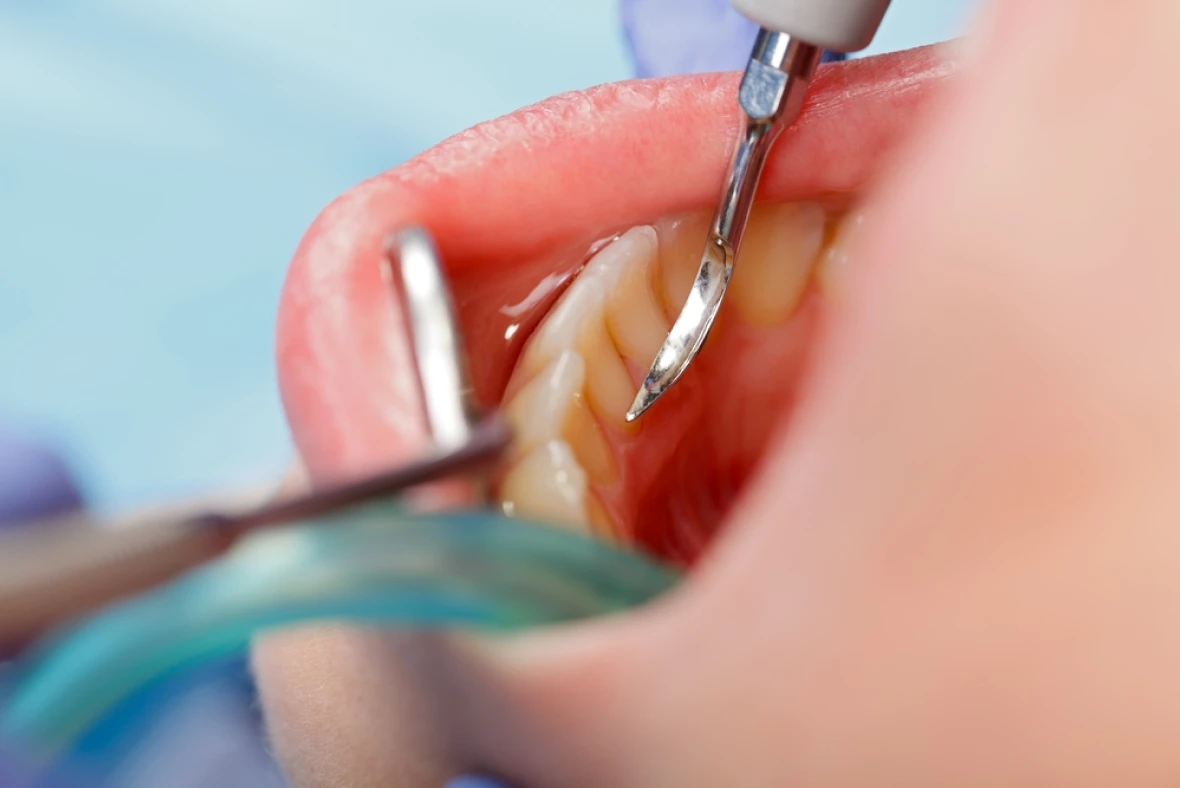

歯周病

歯ぐきが腫れる・歯がぐらぐらする

歯周病は、成人の方の8割が歯周病にかかっているといわれています。

歯周病は、ただ単に歯茎が腫れている病気(歯肉炎)ではなく、歯を支えている骨が溶けていく病気であり、歯槽膿漏とも言われます。一度失った骨はなかなかもとには戻らないため、重度になると歯が抜けてきてしまい、非常に怖い病気です。

歯周病は歯の痛みは、最初はほとんどありません、重度の歯周病になってから気づくことがほとんどです。

歯茎がしみる、血が出るなどの症状が無くても、定期的に検診を受けて頂く事をお勧め致します。早めに治療をおこなえば、進行を止めることは可能です。また、重度に進行した歯周病に関しては再生療法や歯周外科などの歯科治療を駆使し、できるだけ歯の保存できるように努めます。